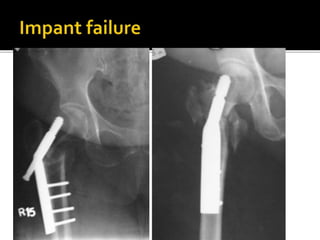

Failed

Subtrochanteric

fracture fixation

with broken DCS

and plate

After 51 days